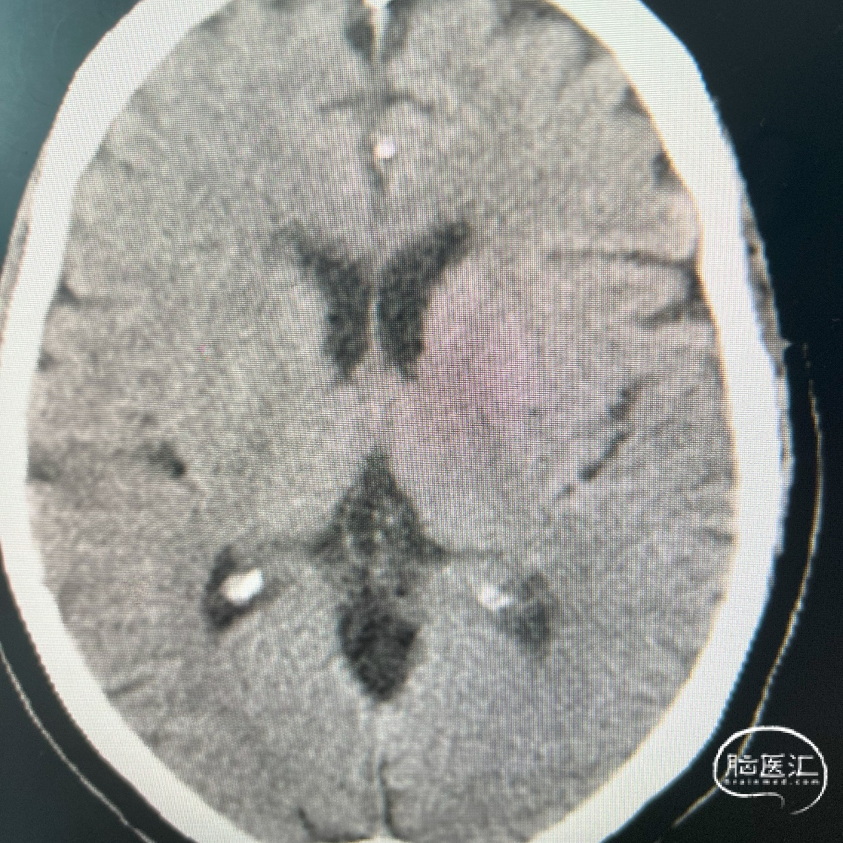

术前DSA影像:

右侧桡动脉穿刺置动脉鞘,泥鳅导丝配合6F 115cm Valent®颅内支撑导管内嵌行至右侧锁骨下动脉近右侧椎动脉起始段处,将导丝配合中间导管上行至椎动脉V3段,撤出泥鳅导丝,手推造影,显示:基底动脉中段可见重度狭窄,狭窄率约80%。

将微导丝头端置右侧大脑后动脉,沿微导丝引入2.0*10mm球囊,小心扩张狭窄段,撤出球囊后造影,原有狭窄较前稍好转,沿微导丝引入支架用微导管置于基底动脉,撤出微导丝,保留微导管,沿微导管引入3.5*15mm Neuroform EZ支架,缓慢释放,复查造影,狭窄较前明显好转,支架贴壁良好。

复查Dyna CT,颅内未见出血及造影剂外渗。

出院情况:

患者手术后头晕症状较入院时期明显减轻(可下地活动,活动时无明显发作,四肢活动自如,一般情况可)。